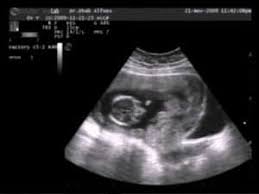

Usia Kandungan 3 Bulan - Hari ini istri saya melakukan checkup kehamilan dengan usg pada usia kandungan 3 bulan / 12 minggu di klinik dr.

Di periode ini, ukuran rahim mengembang dan janin telah mencapai sekitar 83 mm. Obat penggugur kandungan ampuh cytotec asli misoprostol 200mcg yang kami jual 100% asli pfizer di jamin tuntas dan berhasil, terbukti mampu menggugurkan kandungan dari usia kehamilan 1 bulan, 2 bulan, 3 bulan, 4 bulan, 5 bulan sampai 6 bulan. Usia bayi dalam kandungan 3 bulan. Usia kehamilan 12 minggu (kandungan 3~4 bulan) perkembangan janin dan kondisi bumil. Pada usia kandungan ini, pasien akan merasakan sakit yang sedikit tidak berlebihan(sekitar 1 jam), namun hanya akan terjadi pada saat darah keluar merupakan pertanda menstruasi. Selamat datang ke dunia, sayang… beberapa bulan kemudian. Minggu ke 14, pertumbuhan rambut. Hari ini istri saya melakukan checkup kehamilan dengan usg pada usia kandungan 3 bulan / 12 minggu di klinik dr. Hari ini istri saya melakukan checkup kehamilan dengan usg pada usia kandungan 3 bulan / 12 minggu di klinik dr. Dalam video kehamilan usia kandungan 12 minggu ini dijelaskan tentang beberapa hal yang harus diperhatikan oleh ibu hamil. Hal ini dikarenakan pada usia kandungan 3 bulan, janin sudah. Hari ini istri saya melakukan checkup kehamilan dengan usg pada usia kandungan 3 bulan / 12 minggu di klinik dr. Kadang antara hari ke 7 dan ke 9 setelah penghamilan dan plasenta mulai terbentuk.